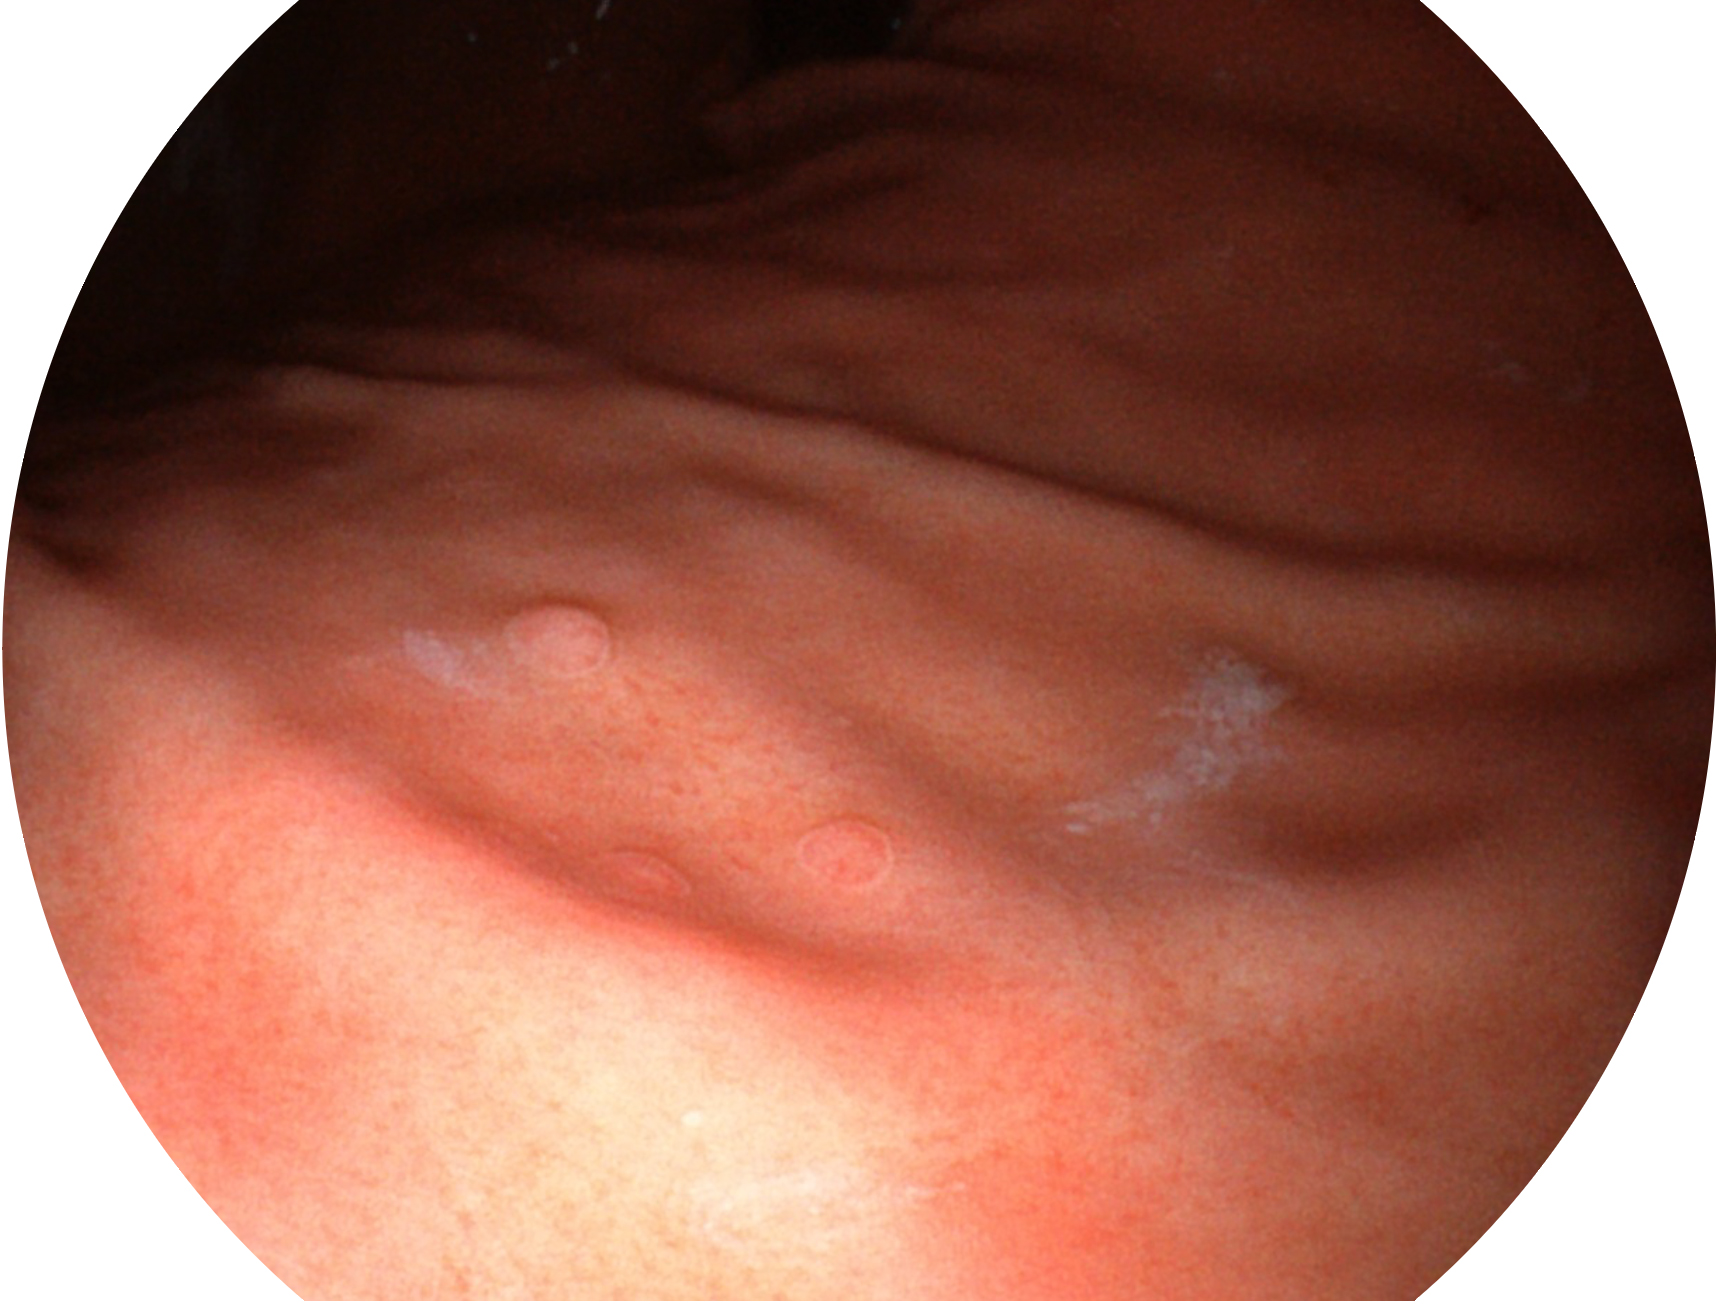

• 白光图像 SFI图像

SFI技术是结合特定光谱照明与数字光谱滤波,实现高亮度特殊光成像。染色模式下,不改变粘液、食物残渣、粪液等基本颜色,在保持与白光照明相似的图像色调的同时突显了图像颜色的红白对比度,且在远距离观察的情况下具备与普通白光模式相同的图像亮度,有助于消化道疾病的大范围扫查和早癌筛查。